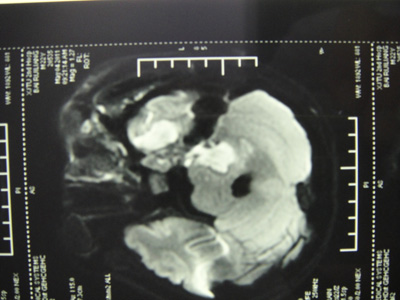

5月3日我院干一科收治一名22岁男性患者。该患者入院前15天在东莞打工时突然发病,高烧,头晕头痛,恶心呕吐,意识模糊,间断抽搐,咽痛,言语不清,左眼肿痛,视物模糊,四肢无力。在当地医院发现血糖高,测随机血糖为18mmol/L,尿中有酮体。腰穿脑脊液压力高,细胞数高,潘氏实验阳性。头颅MRI示左侧颞叶、桥脑、桥小脑脚异常信号影。在当地医院按“1.颅内侵袭性真菌感染 海绵窦综合征 2. 1型糖尿病并酮症酸中毒3.真菌性败血症 4.左上腭真菌感染”,予“伊曲康唑、阿昔洛韦、头孢他啶、甲泼尼龙琥珀酸钠、甘露醇”等药物治疗后,症状缓解不明显,遂来我院求治。

入院时患者病情危重,仍发热,体温38.7度,一般情况差,嗜睡,营养不良,半月余体重减轻约20Kg,左眼肿胀、眼球突出,左眼睑不能闭合,左眼仅可辨认指数,口腔疼痛,上腭部可见大片黑色坏死组织。查体:左侧第2-8对颅神经均受损,交叉瘫,右侧肢体肌力Ⅴ级差,右侧Babinski’s征阳性。左眼球突出,眼球活动受限,左侧球结膜充血、水肿,角膜水肿、浑浊。入院后干一科何娅主任高度重视,立即成立抢救小组,积极开展救治工作。经多部位多次活检,标本送涂片、病理、培养,在口腔坏死组织中发现毛霉菌菌丝及孢子,且培养有金黄色葡萄球菌和鹑鸡肠球菌(天然耐万古霉素),确诊为鼻眶脑毛霉菌病合并细菌感染,结合临床及影像学检查发现该患者病菌侵袭范围相当广泛:波及鼻腔、鼻窦、眼眶、小脑、桥脑及颞叶。该病例非常罕见,病情十分凶险,死亡率极高,文献报导鼻眶脑毛霉菌病死亡率高达97%-100%。因病变范围广,单纯药物治疗效果不佳,必须清除原发灶才能控制病情进展。